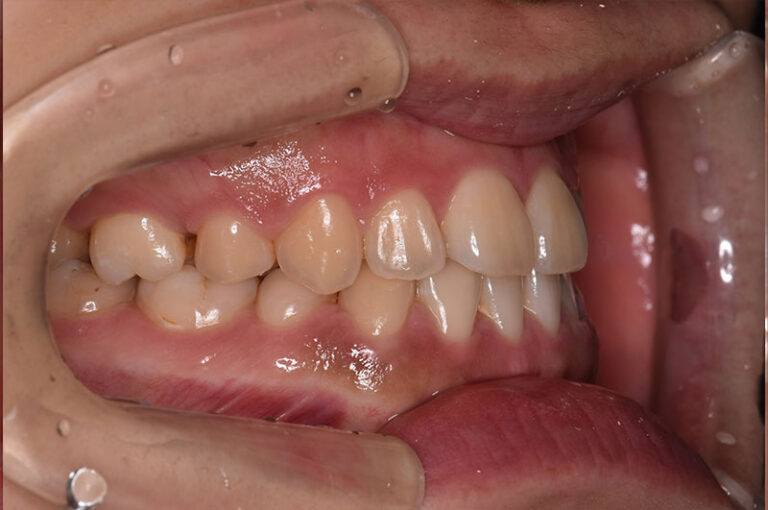

今回は反対咬合に対して、外科手術を行わずに矯正治療のみで改善した成人の症例をご紹介します。

「反対咬合=手術が必要」と思われがちですが、噛み合わせの状態によっては、今回のように矯正治療だけで改善が可能なケースもあります。

治療前後の変化を実際の症例写真でご覧いただくことで、

反対咬合がどのように改善するのかを、イメージしていただければと思います。

症例の概要(手術なし・成人の反対咬合)

術前

術後

| 主訴 | 反対咬合 |

| 初診時年齢 | 24歳 |

| 治療内容・使用した装置 | 頬側ブラケットを用いた永久歯全体の矯正治療、アンカースクリュー |

| 抜歯の有無 | 左右下顎第一小臼歯、左側上顎第二小臼歯抜歯 |

| 治療期間 | 約24ヶ月 |

| 費用 | 総額819,500円(税込) (相談料、検査料、診断料、動的治療費、抜歯費、アンカースクリュー埋入、除去費、保定期間料等含む) |

| 治療に伴うリスク・副作用 | 歯の移動に伴う痛み、上下顎前部の歯根吸収、装置による口内炎、ブラッシング不良によるむし歯、歯周炎 |